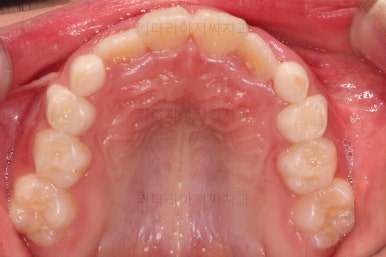

1. 초진

부산어린이교정 키다리아저씨치과에 처음 내원했을 당시의 입안의 모습입니다.

앞니가 거꾸로 물리는 전형적인 앵글씨 3급 부정교합 환아의 모습이었습니다.

아직 유치가 많이 남아 있었꼬, 아래 앞니는 4개가 영구치 맹출, 윗니는 2개가 영구치 맹출 상태였습니다.